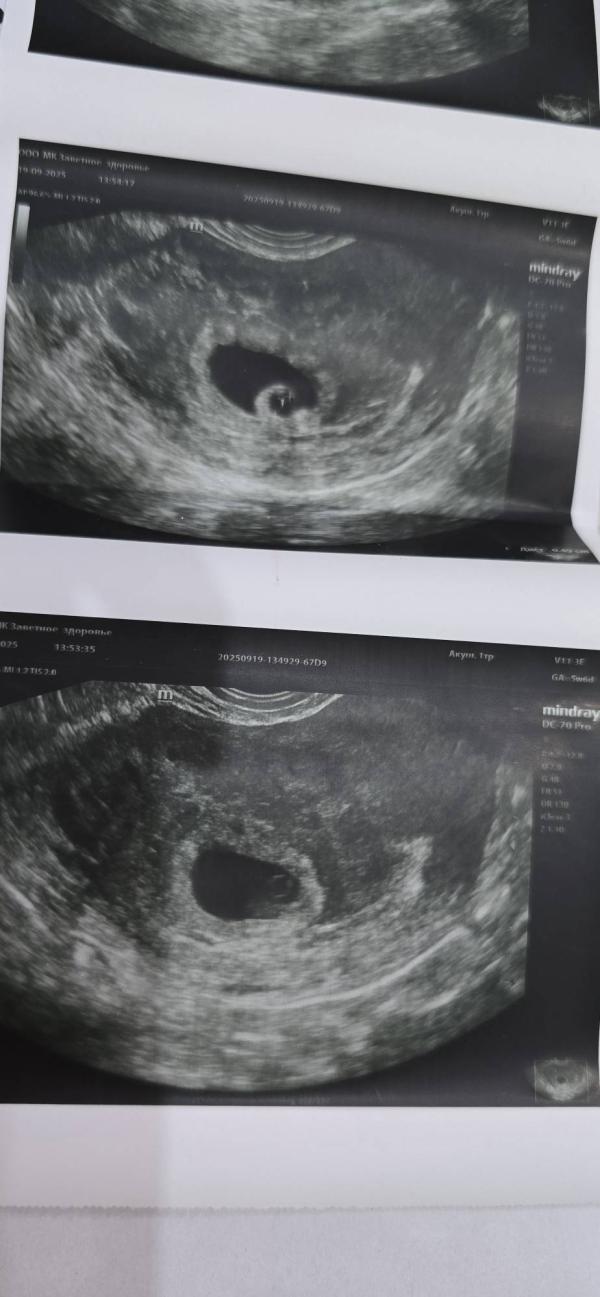

Посмотрите пожалуйста снимки с узи, сверху это хорионический бугорок, а снизу это и есть уооечко с брилиантиком мой?